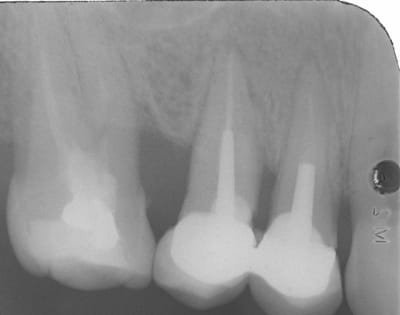

bien voir quoi ? qu'est'u dis ?

regarde sur la molaire , j'ai différé l empreinte de 7 jours.

la photo est le jour de l'empreinte , or le jour de la taille j'etais juxta voire infra .

si j'avais pris l'empreinte le meme jour je l'aurais eu gros...